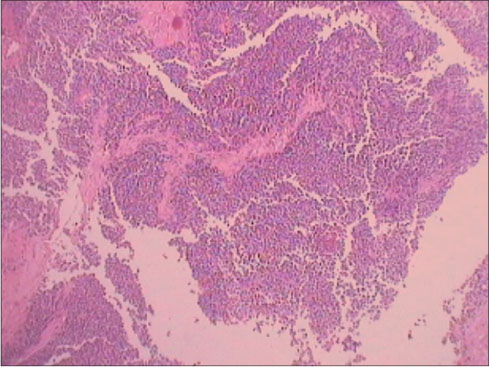

Of the 11 patients, four patients had ES, five extraosseous Ewing?s sarcoma (EES), one with primitive neuroectodermal tumor (PNET), and one with Askin?s tumor. Two had associated comorbidities, spherocytosis and bronchial asthma. The patient with Askin?s tumor developed scalp and leptomeningeal metastasis and succumbed. All 11 patients were IHC proven, and all of them were CD99 positive [Figure 1], [2]. Five patients were vimentin positive and two were neuron-specific enolase positive along with CD99 (MIC-2). Five patients had multiple metastases at the time of presentations, of which four poorly responded to chemotherapy and succumbed very early during the course inspite of compliant treatment, while one patient still continues to follow-up. The two patients who had paraspinal ES developed acute-onset paraparesis and incontinence which progressed to paraplegia within a couple of weeks. Among them, the child was lost to treatment follow-up, while the other patient underwent debulking surgery and was initiated on adjuvant chemotherapy but died after 2 weeks. There were two patients who had a lag time of >2 years to develop metastasis who are still on regular review [Table 1]. Of the 11 patients, only four continue to review in our outpatient clinic while six succumbed and one patient was lost to treatment follow-up. Of the 11 patients, only one patient received radiation to primary site after six courses of chemotherapy, but yet after 3 months, he developed orbital metastases which were cytologically proven.

|?Figure. 1? Low-power image of H and E stain

|?Figure. 2? High-power view of H and E stain